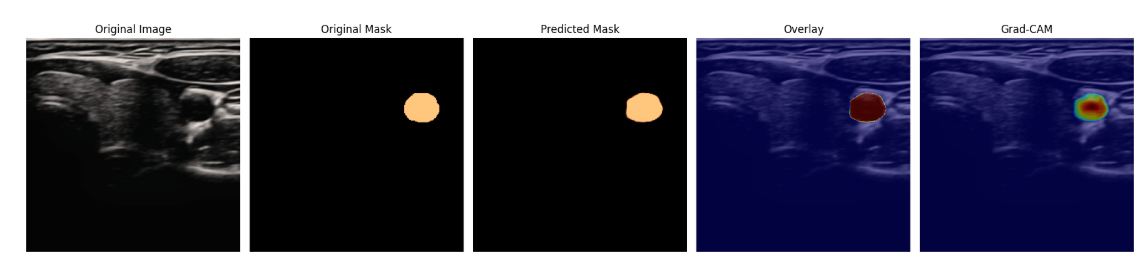

预测的部分结果展示: